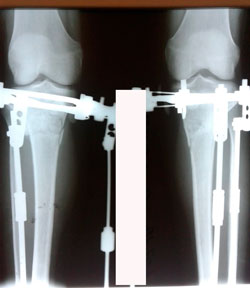

Исходник - 38 лет.

Дата операции 23.03.2020

Вложения

image-01-04-20-11-29-5.jpg

image-01-04-20-11-29-3.jpg